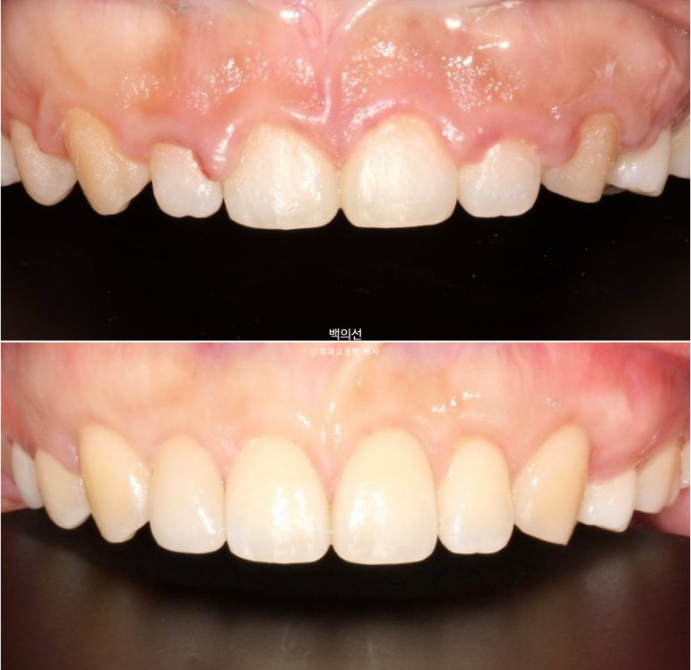

이제 클리피씨 브라켓을 떼고 잇몸성형과 왜소치 라미네이트를 할 차례입니다.

잇몸성형 직후 모습입니다.

잇몸성형 회복기를 거쳐 이제 라미네이트 직전 모습입니다.

왜소치에 무삭제 라미네이트까지 들어간 모습입니다.

어느쪽이 자연치이고 어느쪽이 왜소치 라미네이트 일까요?

25.07

정답은 파란 화살표 치아가 바로 젤라미입니다.

왜소치는 무삭제 라미네이트 젤라미로 깔끔하게 수복되었습니다.

교정 직후 잇몸성형 전과 잇몸성형 후 모습입니다.

아름다운 치아비율과 스마일라인이 돋보입니다.